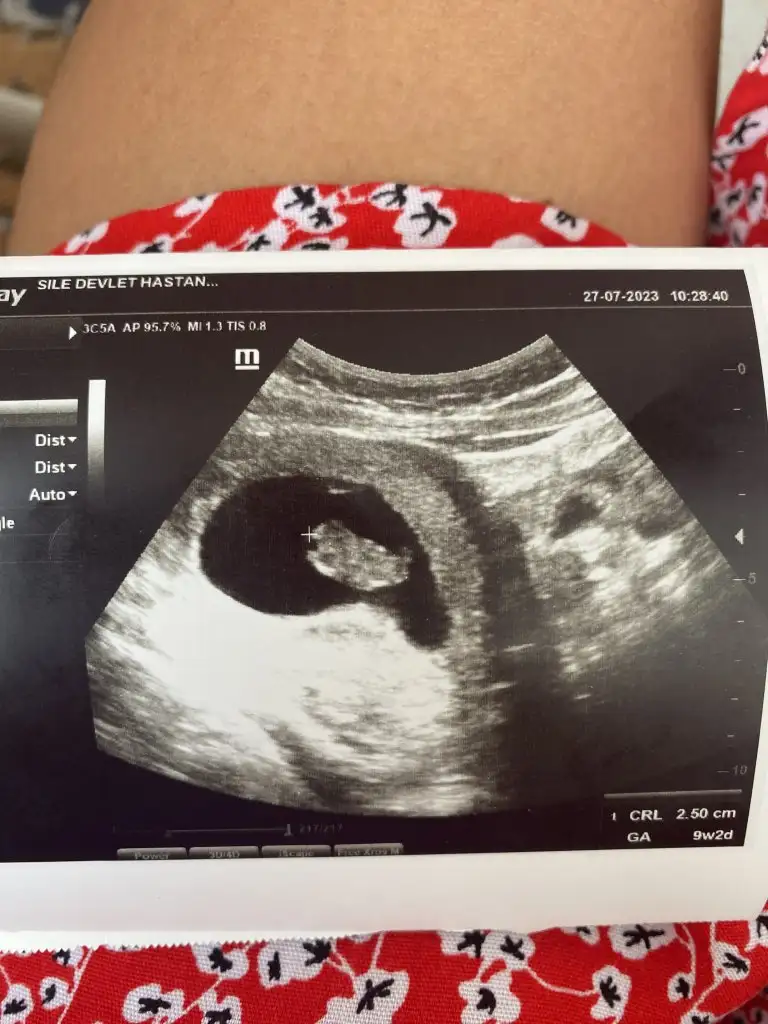

Merhaba rica etsem bizede bir tahmin yapar mısınız?Rica ederim canım ne demek biz sadece tahminde bulunuyoruz. Anne ne hissederse genelde o olur diyorlar belki sen dogruyu hissediyorsundur canım saglıkla gelsin inşallah![]()

Canım kız bebek gibi ama tam emin olamadımMerhaba rica etsem bizede bir tahmin yapar mısınız?![]()